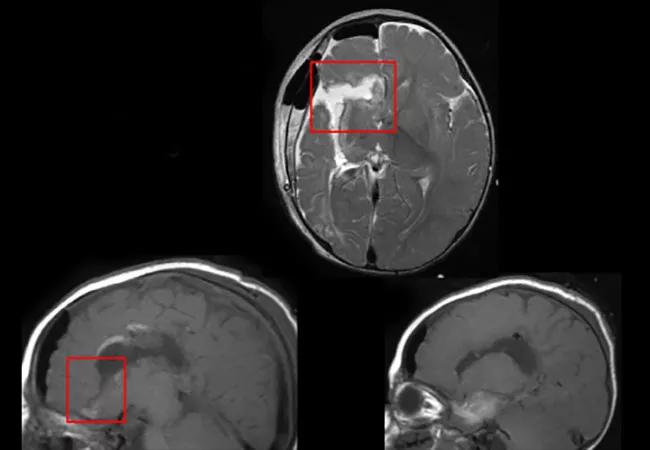

After Disconnective Hemispherectomy, Epileptiform Discharges Are Common on the Operated Side in Seizure-Free Patients

Most pediatric patients who are seizure-free after successful disconnective hemispherectomy continue to have abnormalities evident by electroencephalography (EEG) in the disconnected hemisphere. Nevertheless, many of these patients can be weaned off antiseizure medications (ASMs) with no recurrence of seizures.

Disconnective hemispherectomy is an important option for selected patients with drug-resistant epilepsy. Cleveland Clinic’s experience from 170 patients who underwent the surgery between 1997 and 2009 resulted in about two-thirds being seizure-free after hemispheric surgery (Neurology. 2013;80:253-260).

However, a wide spectrum of abnormalities in the disconnected hemisphere may be seen on EEG after the operation. Although EEG abnormalities usually help determine whether a patient should be weaned off ASMs following surgery, the nature of these abnormalities and how they correlate with clinical outcomes have not previously been well characterized in the setting of disconnective hemispherectomy.